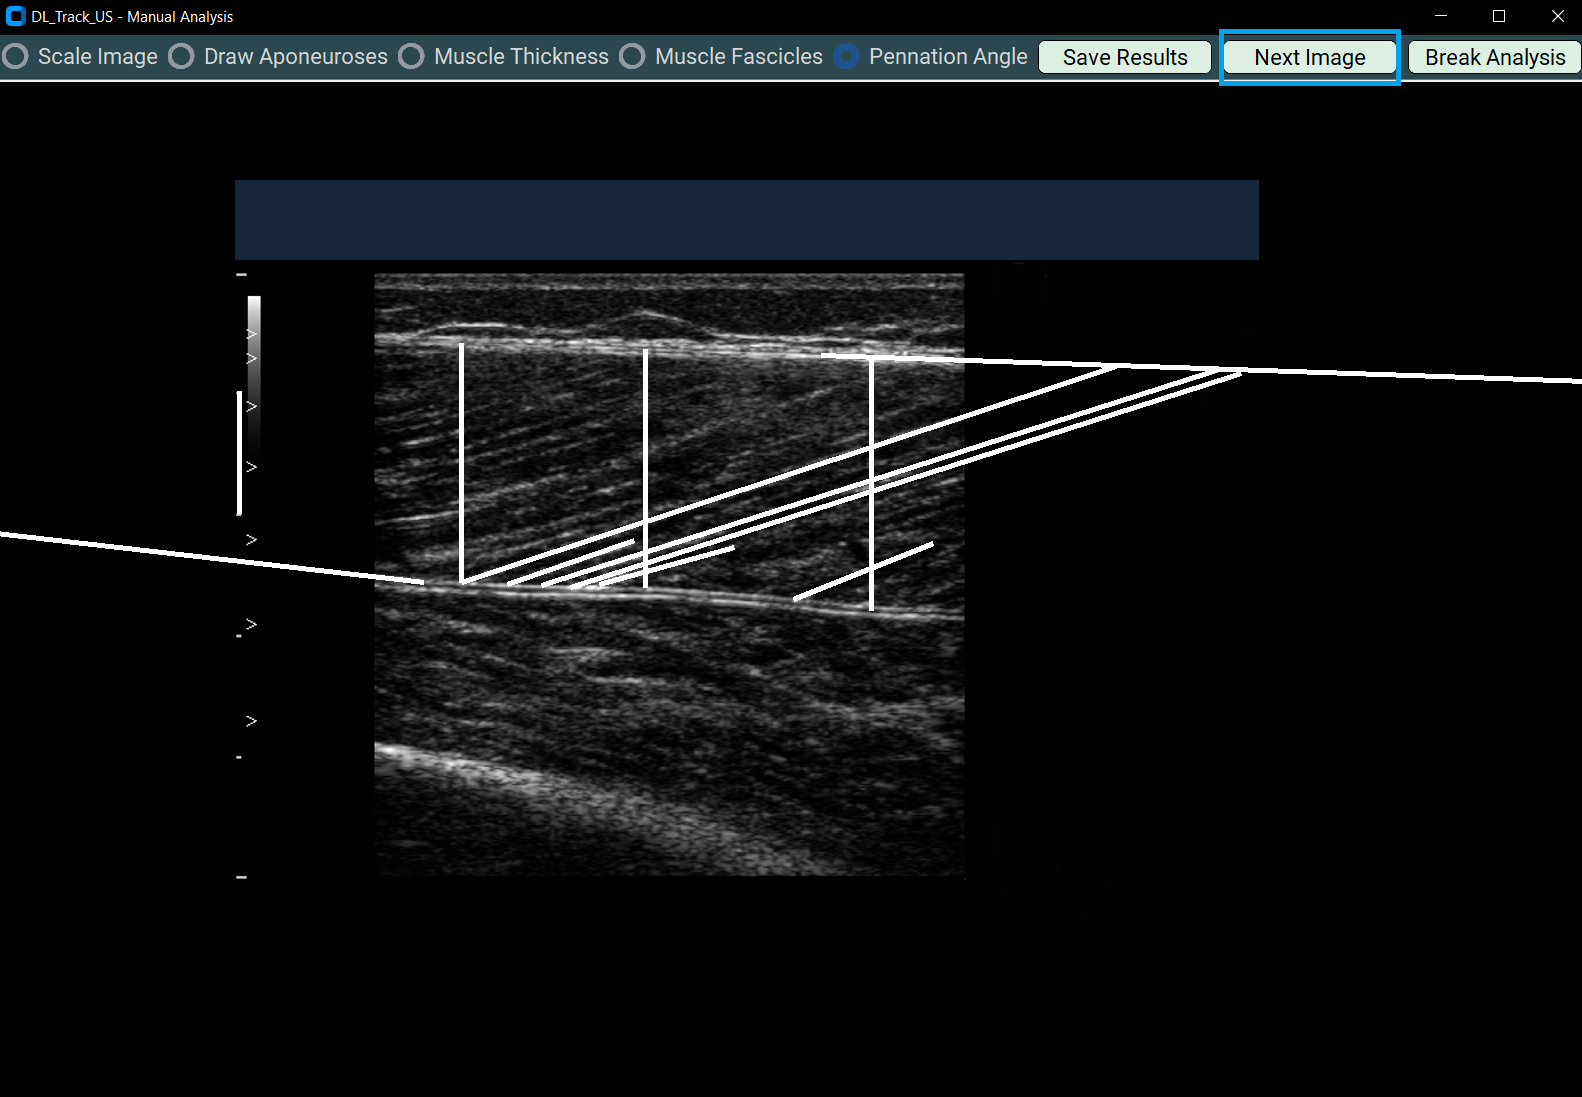

4.5 Measuring Pennation Angles¶

- Select Pennation Angle.

- Draw at least three pennation angles:

- Each must have two segments:

- Along the fascicle

- Along the deep aponeurosis